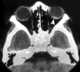

Strabismus

Strabismus is a condition in which the eyes do not properly align with each other when looking at an object. The eye that is focused on an object can alternate. [Source: Wikipedia ]